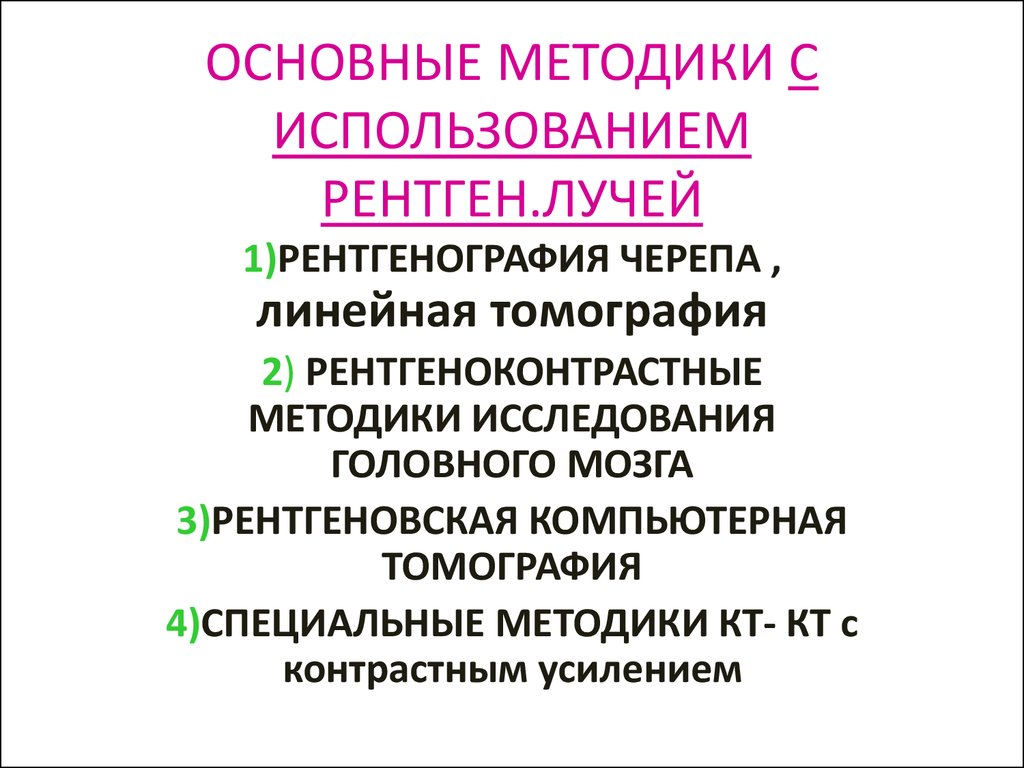

Лучевая диагностика в неврологии презентация - 88 фото